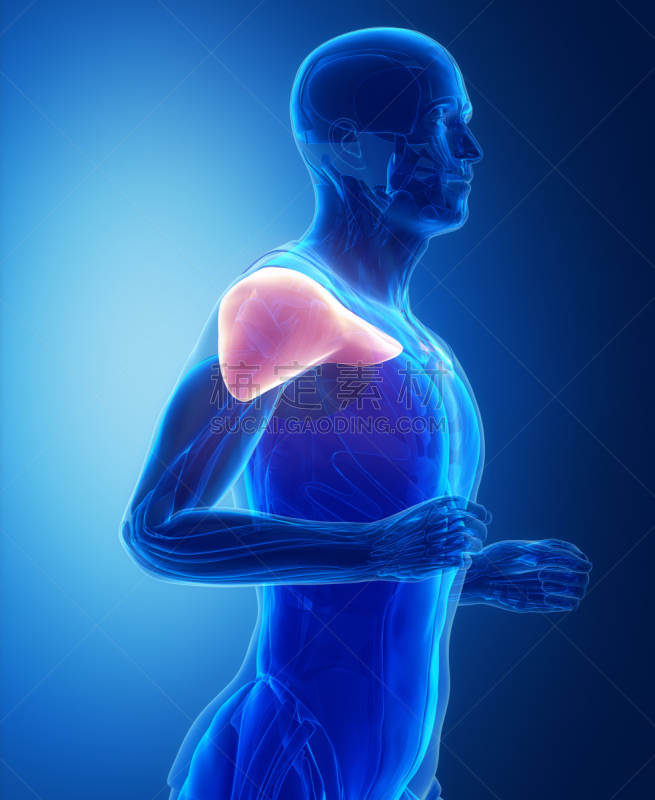

肌肉系统解剖学侧视图详情

肌肉系统解剖学侧视图详情